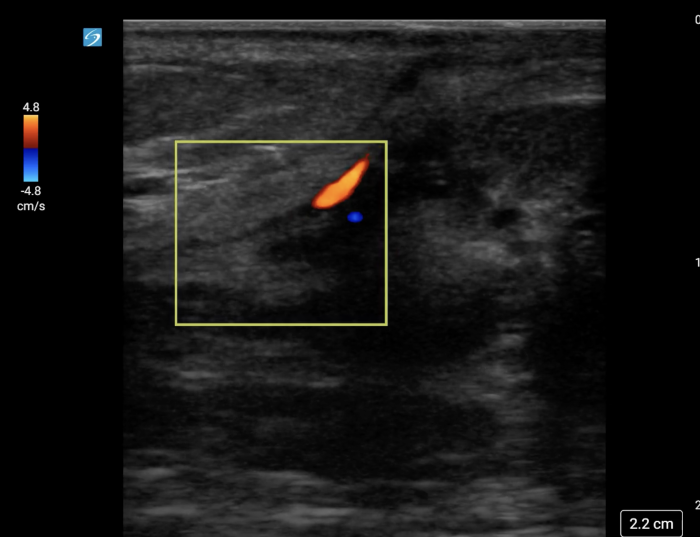

In your first image (Image 1), you realize there is no flow with color Doppler. Additionally, you find a torsed cord complex (Image 2), also known as the “corkscrew sign.” You consult Urology who is busy in the operating room with another case. You decide to perform a manual detorsion due to your concern for testicular atrophy and risk of infertility. Using the open book technique, you get relief of pain and return of vertical positioning of the testicle after two rotations. On your repeat testicular POCUS with color Doppler you obtain these images (Images 3 and 4), which demonstrate venous and arterial flow throughout the testicle. The cord is now untwisted and appears linear in orientation.

Torsion - image 3_crop.pngImage 3. Color Doppler demonstrating intratesticular flow toward and away from the probe.